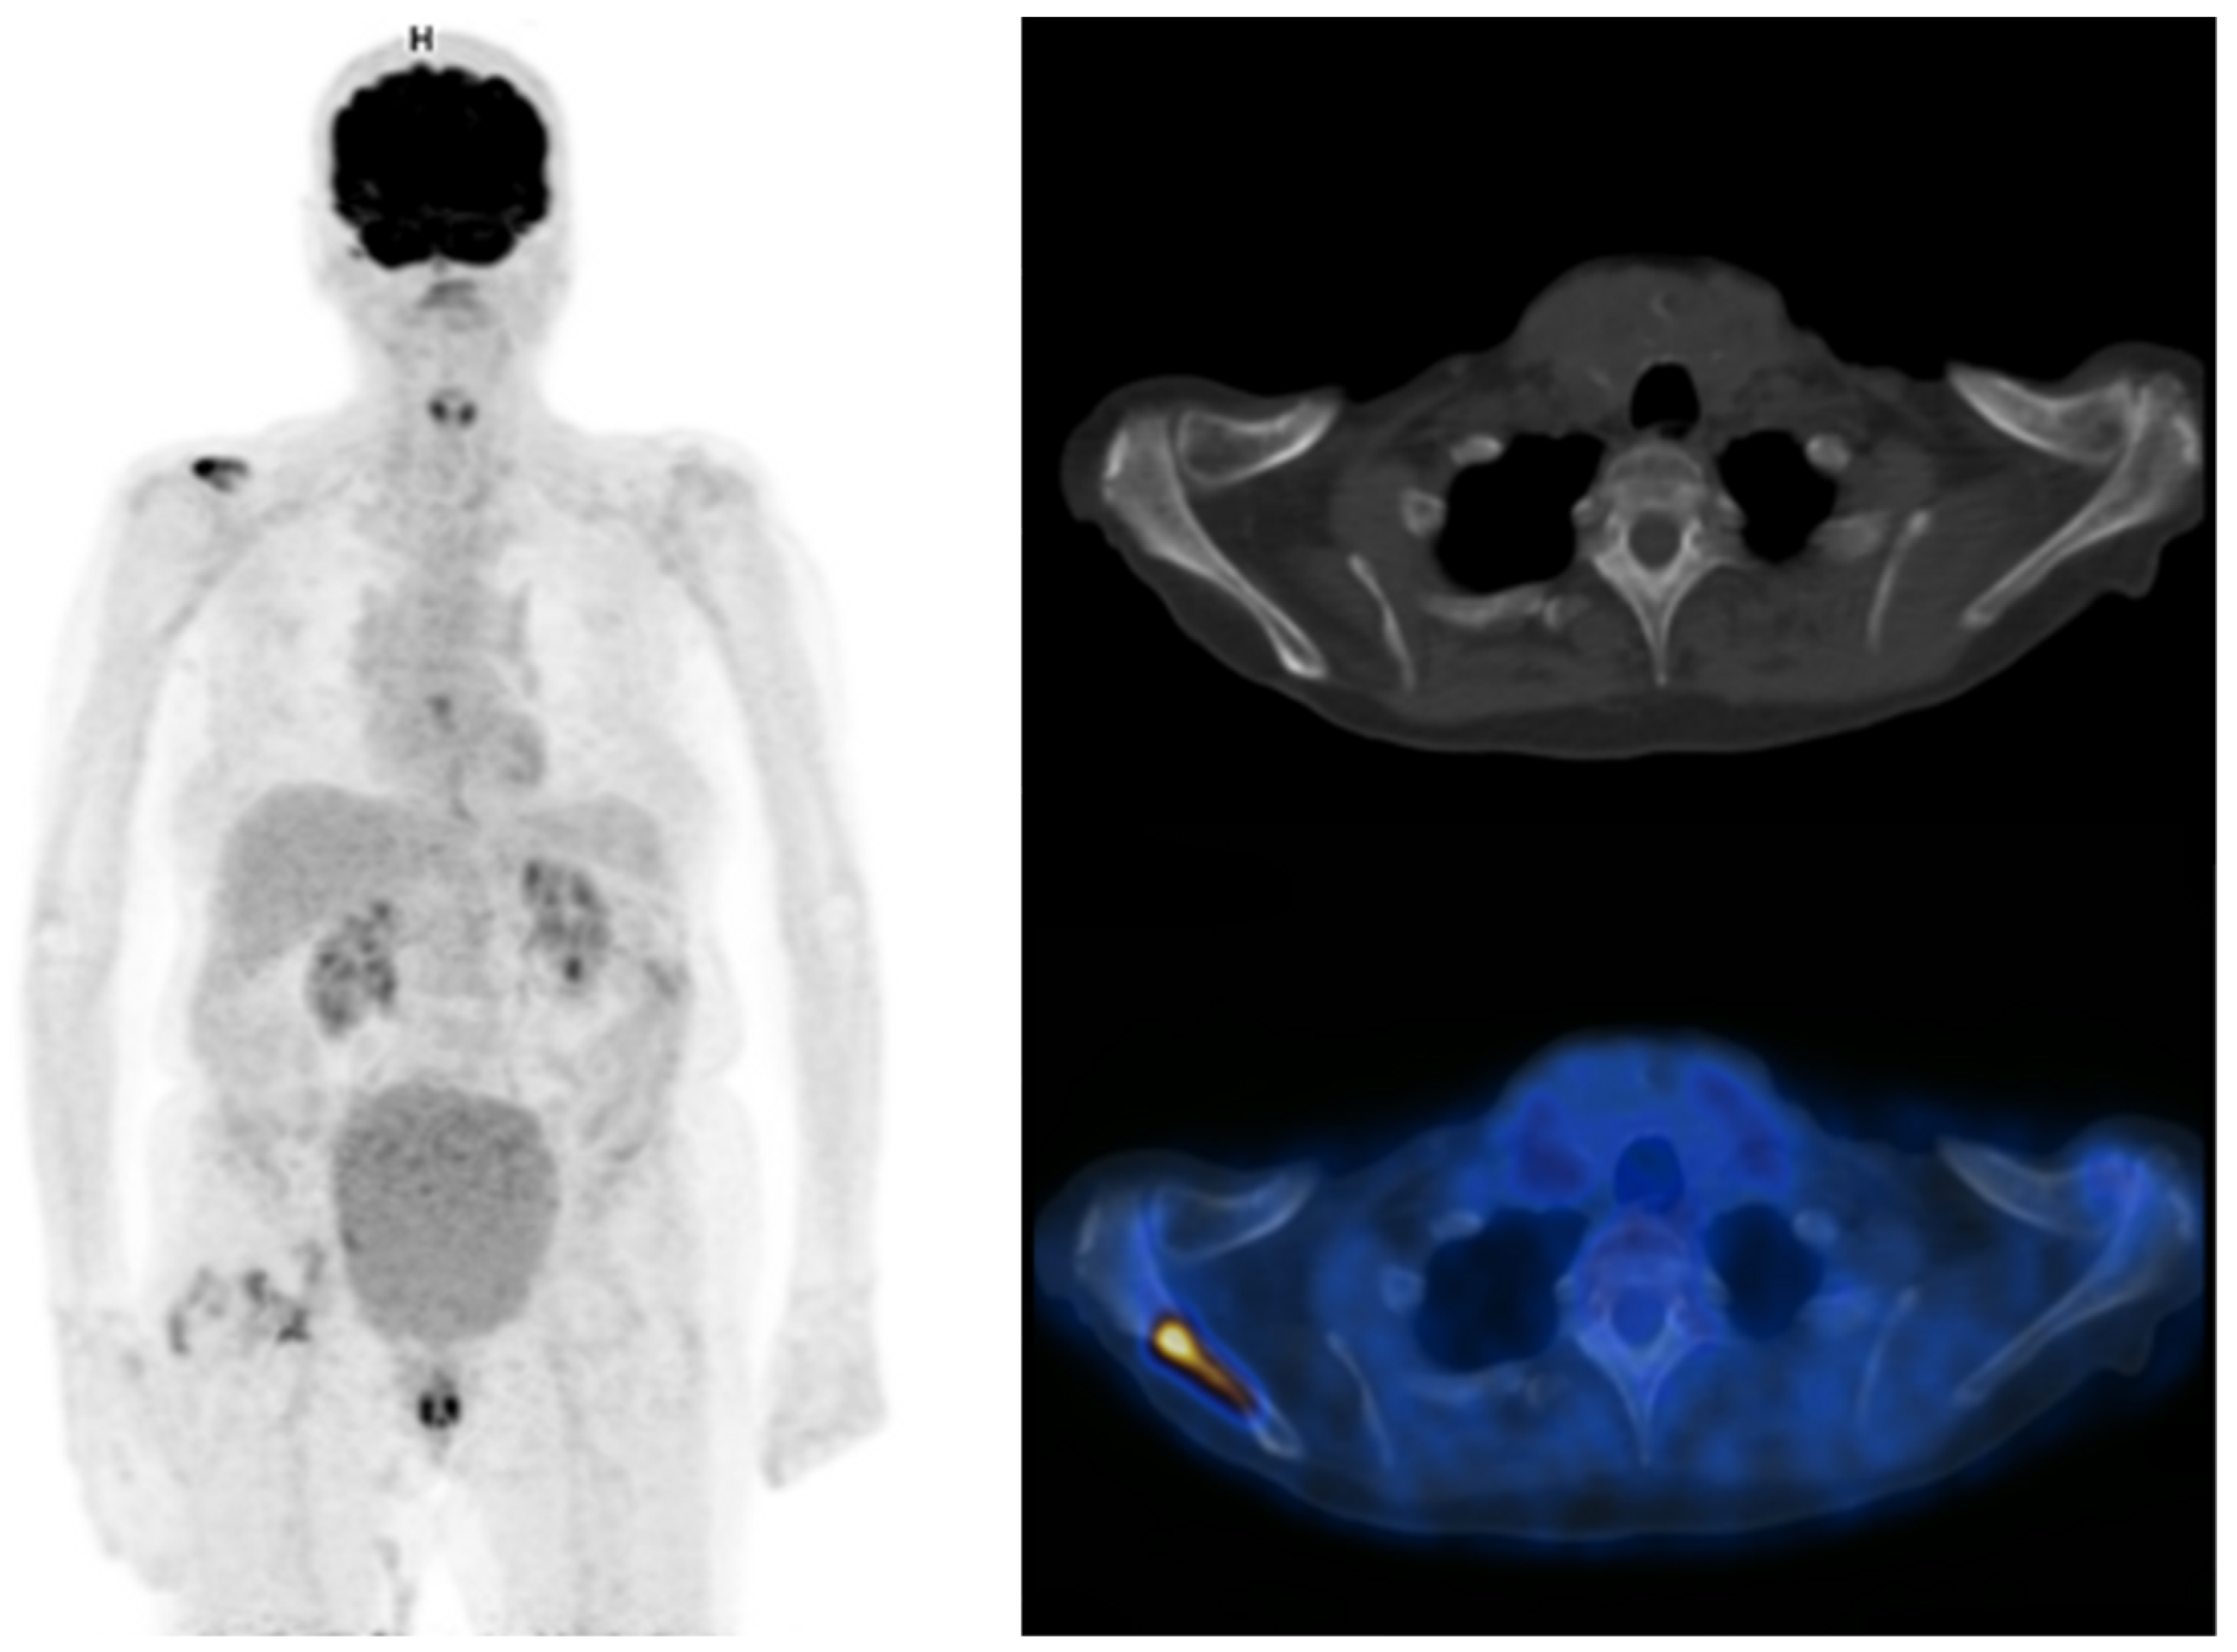

- Rouanne, M.; Alhammadi, A.; Vilain, D.; Radulescu, C.; Lebret, T. Value of positron emission tomography in diagnosing synchronous penile metastasis from urothelial bladder cancer. World J. Surg. Oncol. 2015, 13, 276. [Google Scholar] [CrossRef]